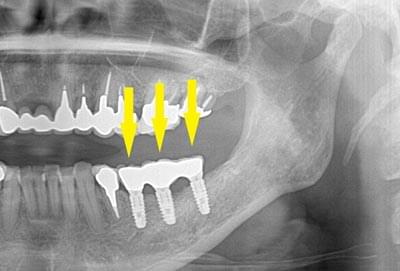

写真は患者様の治療前のレントゲン写真です。右上顎の大臼歯を喪失し、延長ブリッジを装着されていたのですが、支える歯が破折してしまい、抜歯が必要となりました。ここにインプラント治療を行うには、骨が薄くて、困難な状態でした。

CTで見ると、骨が薄いのが良く分かります。黄色の矢印の部分、白く写るのが骨で、矢印のある黒い部分が上顎洞という空洞です。

この空洞部分に、人工骨を入れて、閉鎖しておくと、数か月ほどで骨に置き代わっていき、インプラントを埋入できるだけの骨量になります。サイナスリフトが終了して、数か月経過し、薄かった骨が十分な厚みができたCT画像です。黄色矢印の部分、白く写る骨が増えています。

サイナスリフトを行って、8か月後に、インプラントの埋入手術を行いました。骨が十分にあったので、通常の長さのインプラントが埋入できました。